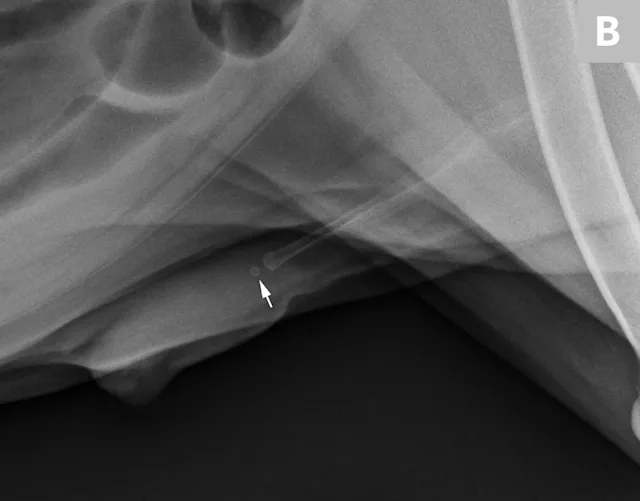

FIGURE 11A

Lateral radiograph of a male dog collimated to include the urinary bladder and os penis. Note the well-defined mineral opacity just proximal to and at the same level as the base of the os penis—a separate center of ossification (arrow). Also note the two soft tissue opaque nodules summating with the prepuce, presumed to be small nipples (arrowheads).

A separate center of ossification associated with the os penis may mimic a urethral calculus (Figure 11 A and B). A separate center of ossification can be seen at either end of the os penis and will be in line with the os penis. A calculus within the penile urethra would be seen ventral to the os penis in the location of the urethra. Contrast urethrography can be a helpful way to differentiate between a separate center of ossification and urethral calculus (Figure 11C).